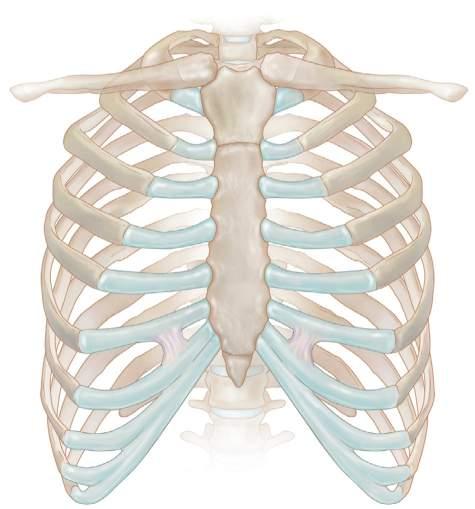

Thecartilageofthetrueribsarticulateswiththesternumviathecostosternal joints(Fig.1.3).Thecartilageofthefirstribarticulatesdirectlywiththemanubriumofthesternumandisasynarthrodialjointthatallowsalimitedgliding movement.Thecartilageofthesecondthroughsixthribsarticulateswiththe bodyofthesternumviatruearthrodialjoints.Thesejointsaresurroundedbya thinarticularcapsule.Thecostosternaljointsarestrengthenedbyligamentsbut

Fig.1.3 Theanatomyofthechestwall.(FromWaldmanS. AtlasofPainManagementInjection Techniques.ed.4.St.Louis:Elsevier;2017[Fig.99-3].)

Clavicle

Costal cartilage

Costosternal joint

Costochondral joint Jugular notch of sternum

canbesubluxedordislocatedbyblunttraumatotheanteriorchest.Posteriorto thecostosternaljointarethestructuresofthemediastinum.Thesestructuresare susceptibletoneedle-inducedtraumaiftheneedleisplacedtoodeeply.The pleuralspacemaybeenterediftheneedleisplacedtoodeeplyandlaterally,and pneumothoraxmayresult.

Sternum Costosternal joints